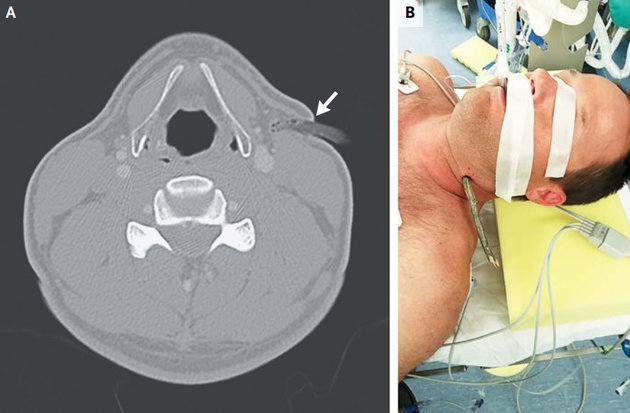

Vận động viên hiện chưa xác định danh tính này bị một cành cây có đường kính 2 cm đâm vào cổ sau khi anh ngã xe. Mặc cho cơn đau hành hạ, anh bình tĩnh giữ nguyên vết thương và nhờ một ôtô đưa đến Bệnh viện Đại học New Mexico cách đó 32 km để chữa trị.

Kết quả chụp CT cho thấy cành cây đâm sâu 1,6 cm trong cổ bệnh nhân, rất may là không chạm đến các dây thần kinh, đường hô hấp và động mạch cổ. Bác sĩ Lev Deriy thuộc Bệnh viện Đại học New Mexico, chữa trị cho vận động viên này, nói rằng anh cực kỳ may mắn mới không bị chấn thương nghiêm trọng nào sau tai nạn trên. Người đàn ông này đã được phẫu thuật lấy cành cây ra khỏi cổ và nhanh chóng xuất viện.